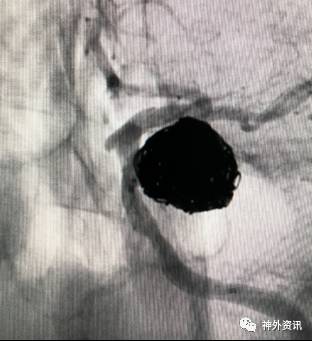

猪尾塑形

猪尾左行和右行

微导管尾端向下直立,头端向前弯曲时,头端相对左偏为左行,右偏为右行。

指向下方的颈内动脉眼段或床突段动脉瘤(颈动脉窝动脉瘤)

指向下方的颈内动脉后交通段或脉络膜段动脉瘤

(1)左侧颈内动脉-猪尾左行

(2)右侧颈内动脉-猪尾右行

病例一

病例二

病例三

病例四